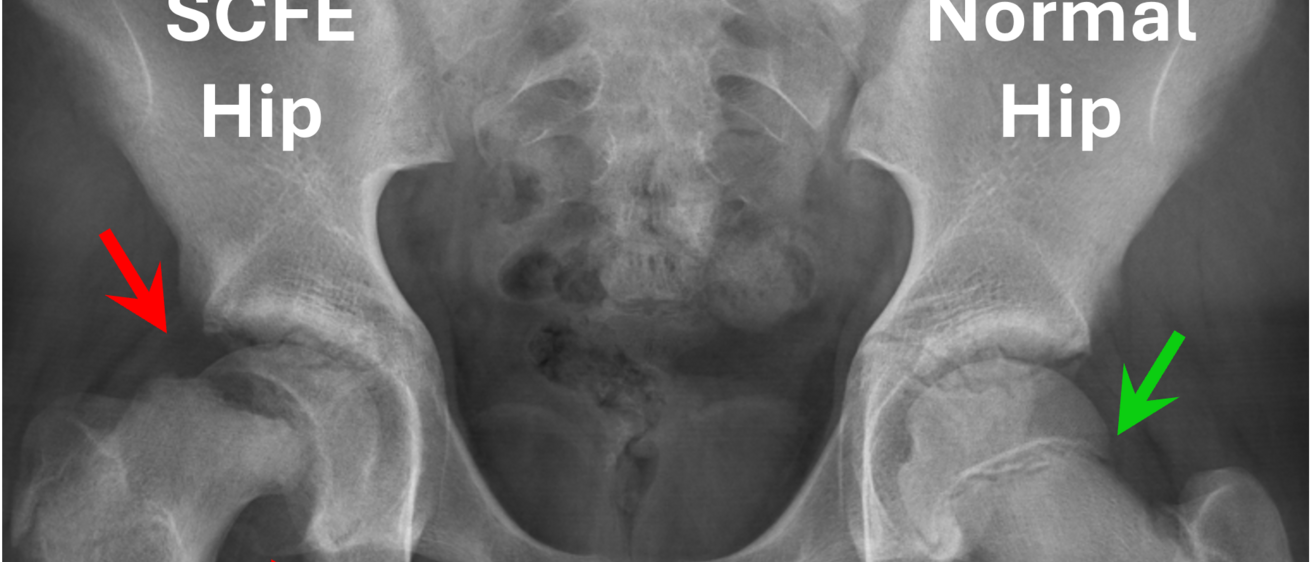

Slipped capital femoral epiphysis (SCFE) is a common disorder affecting adolescent patients in which the epiphysis separates from the metaphysis of the femoral neck. The proximal femoral epiphysis remains in the acetabulum, while the metaphysis rotates anteriorly, externally, and into extension. It can be a devastating injury with necrosis of the femoral head and rapid progression of hip arthritis even when managed urgently and appropriately. Multiple operative interventions have been proposed as possible management options, but these surgical interventions all impart modest morbidity and have shown variable outcomes depending on timing and the type of intervention. Some of the more conservative approaches, such as in-situ pinning, stabilize the hip from further changes in shape, but at the same time make permanent the changes in shape that have occurred to date. This permanently alters the mechanics of the hip and can create extra-articular impingement and intra-articular contact stress elevations, both of which are concerning for premature osteoarthritis development. Bony remodeling of the pinned hip is expected given its skeletal immaturity, but the extent of that remodeling is unpredictable and governs the need for additional surgical procedures to minimize future osteoarthritis risk.